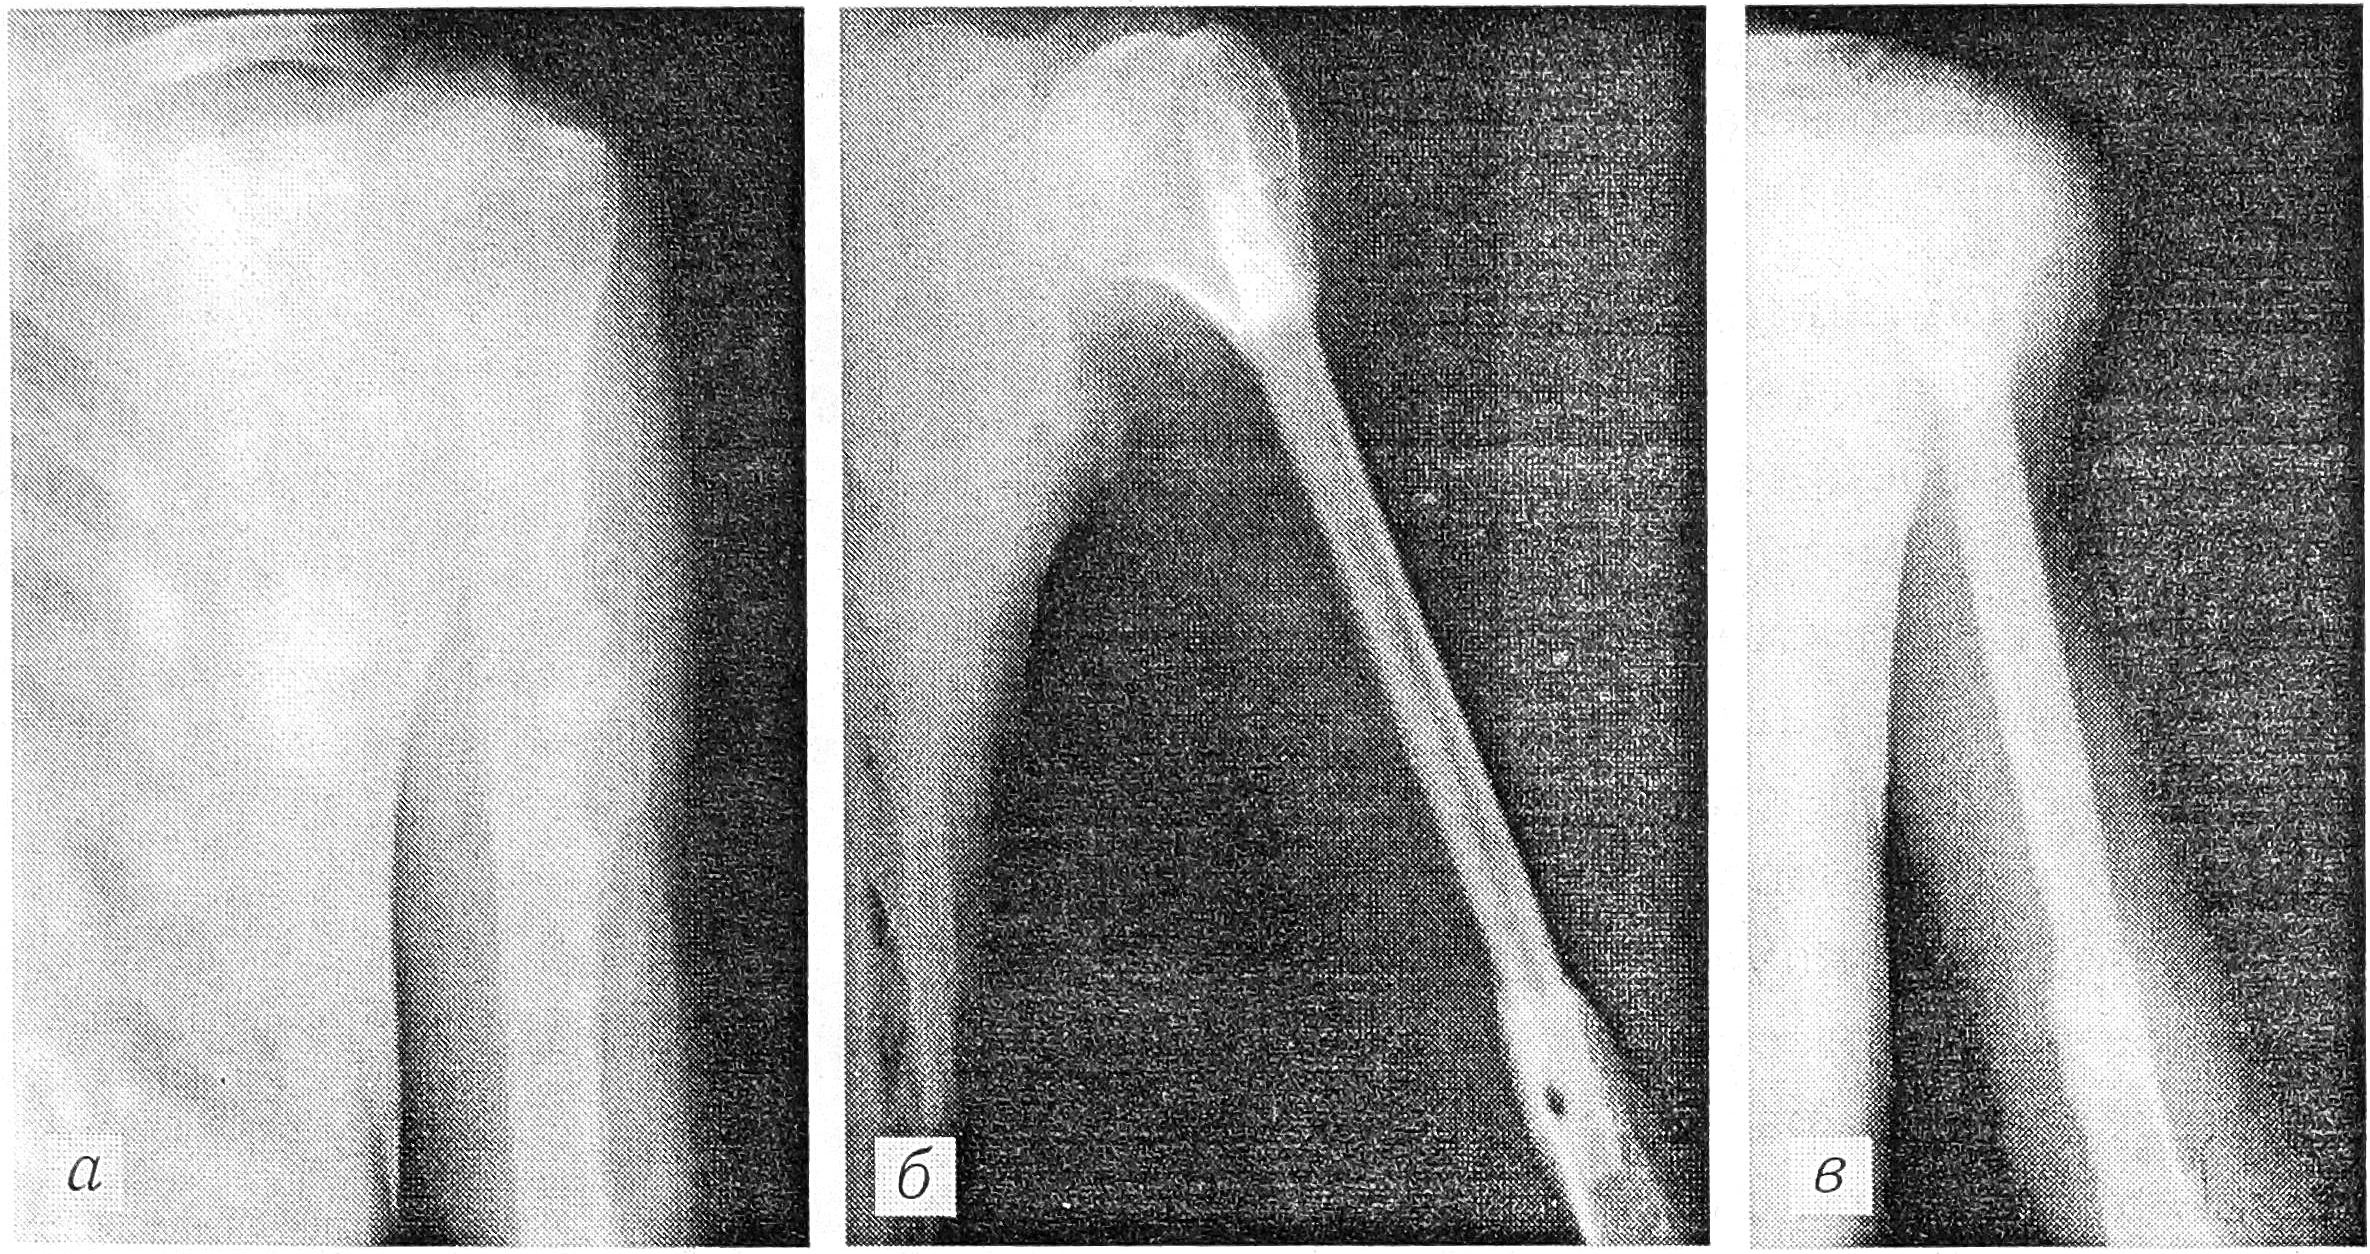

Больной Ш., 19 лет. Диагноз: остеобластокластома левой плечевой кости (рис. 3, а). В ноябре 1990 г. появилась быстро увеличивающаяся в размерах опухоль. 7.05.91 произведена краевая резекция плечевой кости. При гистологическом исследовании удаленного препарата диагностирована остеобластокластома с аневризмальной кистой и признаками озлокачествления. Учитывая данные гистологического исследования и быстрый рост опухоли, проведено комбинированное лечение: предоперационный курс дистанционной гамма-терапии на зону опухоли (суммарная очаговая доза 50 Гр). 3.07.91 выполнена резекция диафиза плечевой кости с одномоментным замещением дефекта фрагментом правой малоберцовой кости на микрососудистых анастомозах. Фиксация проводилась аппаратом Илизарова. Через 3 мес после операции аппарат снят. На рентгенограмме (рис. 3, б) видно полное сращение костных фрагментов. При контрольной рентгенографии через 2 года отмечена выраженная гипертрофия костного трансплантата (рис. 3, с), наступившая под воздействием возрастающей физической нагрузки. Функция руки полностью сохранена (рис. 3, г).

Рис. 3. Больной Ш.: a — рентгенограмма до операции; б — через 3 мес после резекции диафиза плечевой кости с замещением дефекта аутотрансплантатом на микрососудистых анастомозах; в — через 2 года после операции (видна гипертрофия аутотрансплантата); г -— функция руки через 2 года после операции.